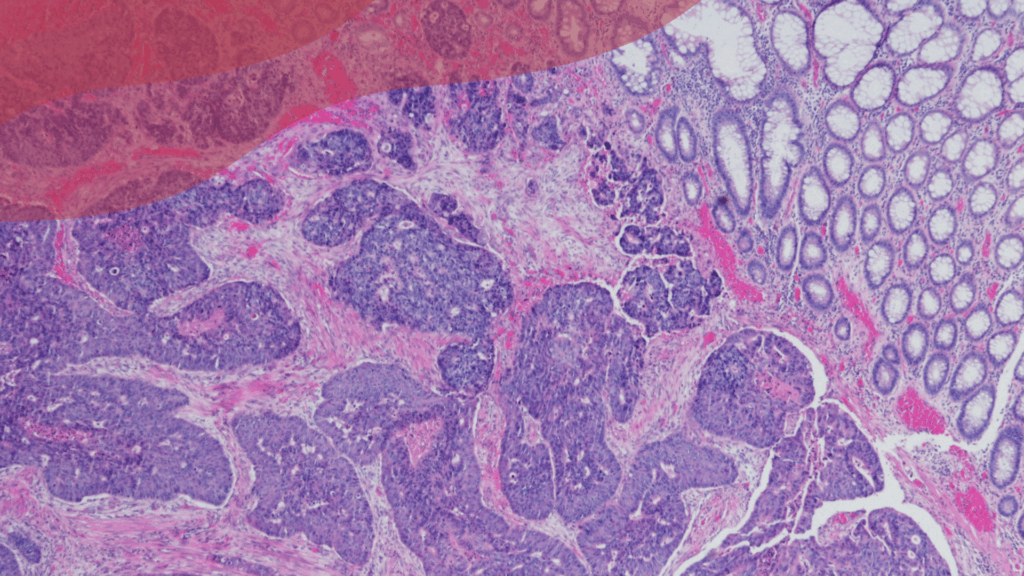

Els tumors neuroendocrins (TNE) constitueixen un grup heterogeni de neoplàsies amb una diferenciació predominantment neuroendocrina. Tot i que les localitzacions més freqüents són el pàncrees, el tracte digestiu i el pulmó, aquest tipus de càncer pot aparèixer pràcticament a qualsevol òrgan del cos, ja que aquestes cèl·lules es distribueixen durant l’etapa embrionària per tot l’organisme. Dins de la categoria de TNE, els més freqüents són els d’origen gastroenteropancreàtic (TNE-GEP), els pulmonars, tumors a la glàndula suprarenal, el carcinoma medul·lar de tiroide i el carcinoma de cèl·lules de Merkel.